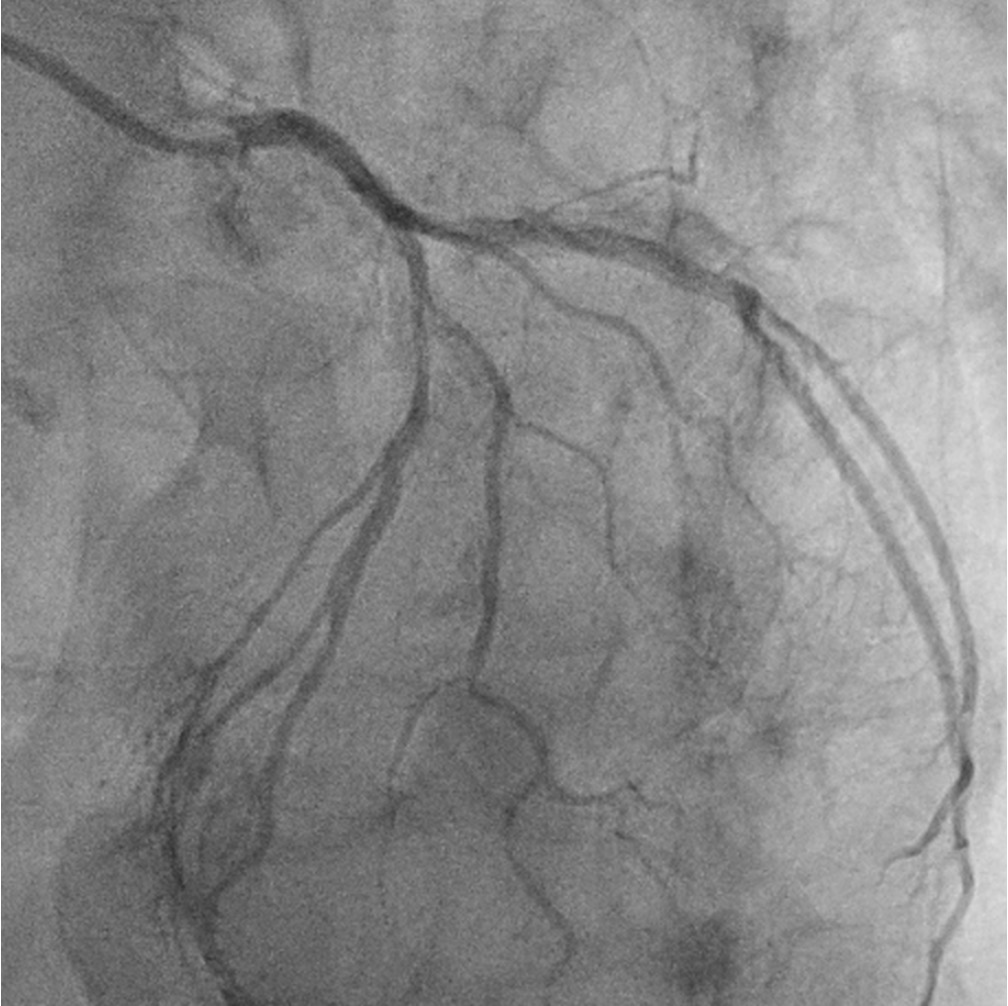

This confirmed severe calcific triple vessel disease. Severe mid LAD diagonal bifurcation stenosis (Medina 1,1,1). Severe LCx ostial and mid stenoses with large ostial calcific nodule. Severe ostial RCA stenosis and distal RCA CTO receiving collateral supply from the septal perforators. CABG was declined due to high surgical risk. After extensive discussions with the patient, his family, and the Vascular Surgical team, high risk vascular and coronary interventions were undertaken.

The Vascular team performed aortoiliac revascularisation to concurrently treat his peripheral vascular disease and allow for femoral access for CHIP. Kissing covered stents were placed from the abdominal aorta to bilateral CIAs and EIAs using the ¡°pave and crack¡± technique with chimney stenting to the IMA. After recovery, single access for Impella CP supported high-risk PCI (SHiP) was performed via the left femoral artery with a 7F sheath through the 14F Impella sheath. Intervention began with the LAD using rotational atherectomy (1.25mm burr) but led to hemodynamic instability despite Impella support, requiring emergency intubation and dopamine infusion. Significant blood loss was noted from the SHiP access due to the inadvertent migration of the PCI sheath proximally, and addressed by repositioning the sheath and transfusion. Once stabilised, the LAD, diagonal, and LCx arteries were treated with rotational atherectomy (1.25mm burr). The LCx had follow up orbital atherectomy, and scoring balloon angioplasty for a large ostial calcific nodule. The left main stem bifurcation was treated with drug eluting stents using OCT guided nano crush technique (3.5/28mm LMS-LAD, 3.5/28mm LCx). The first diagonal and mid LCx were treated with drug eluting balloons (2.5/30mm, 2.5/20mm). Final POT was performed in the LMS (4.0/8mm non-compliant at 18atm). Final OCT and angiography showed satisfactory result with TIMI 3 flow.